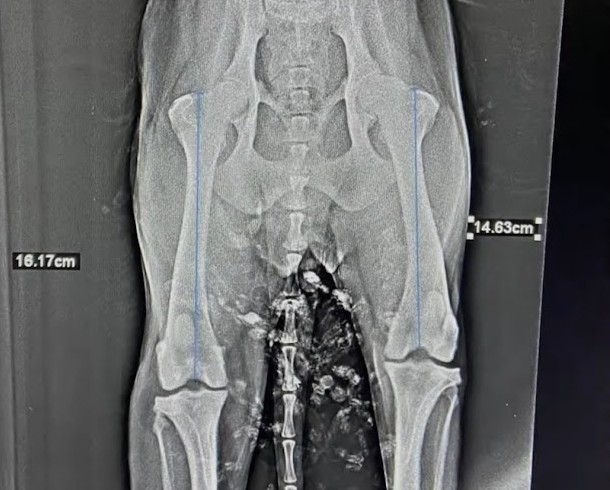

A frightened and confused dog was found, seemingly searching for the owner who had abandoned her. Thankfully, she had no broken bones or dislocations.

Her past injuries included a fractured and healed hip. Despite some minor blood abnormalities, tests for her liver and kidneys came back normal.